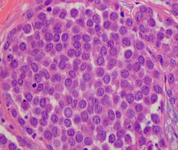

Histopathology of classic lobular carcinoma in situ (LCIS)

Courtesy of Dr Sunati Sahoo, University of Louisville; used with permission